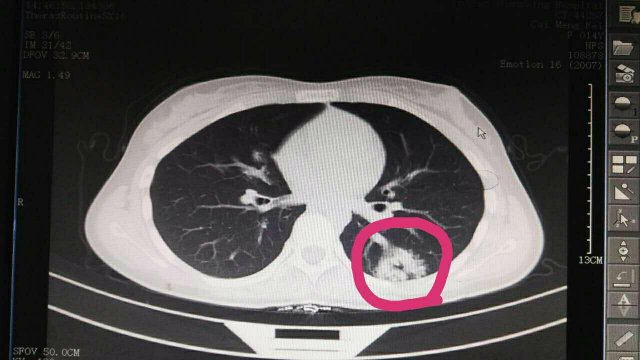

莆田盛興醫(yī)院兒科門診查體發(fā)現(xiàn)一例疑難疾病

蔡**,女,14歲因“反覆頭暈3年余”,求診莆田及莆田各三級(jí)醫(yī)院,做過很多輔助檢查,均未確診,于2017-2-26日就診我院門診,接診是我院兒科林富醫(yī)師,經(jīng)過認(rèn)真仔細(xì)查體,發(fā)現(xiàn)患兒左側(cè)肩胛骨可聞及Ⅱ-Ⅲ/Ⅵ級(jí)收縮期雜音,為明確診斷,即刻請(qǐng)我院莊姞副主任醫(yī)師(原莆田市Di一醫(yī)院NICU主任)會(huì)診,查胸部CT發(fā)現(xiàn)左肺下葉背段血管畸形。莊姞副主任醫(yī)師告訴我們,部分型肺血管畸形如果不認(rèn)真查體是很難查體的到,年輕醫(yī)師能如此仔細(xì)查體,確診多家醫(yī)院未確診的疾病,不得不對(duì)林醫(yī)生豎起大拇指,通過此次經(jīng)歷,可見臨床醫(yī)生必須熟練掌握臨床三基的重要性。